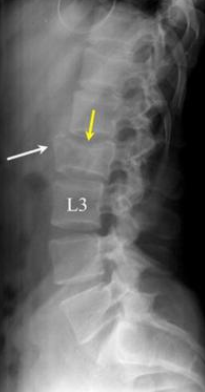

이 사건의 의뢰인은 상대방이 동석한 교통사고 피해자로서 사고 후 요통으로 ○○병원 응급실에 내원하였고 “제2요추폐쇄증후군” 진단을 받았다. 방사선 검사에서 “압박 골절”이 나타났습니다. 부상 초기에 척추의 추가 기형이 진행되거나 신경학적 증상이 나타나면 수술을 준비하고 며칠 동안 경과를 지켜보십시오. 다행스럽게도 통증은 신경학적 증상 없이 차차 가라앉았고, 정형외과를 통한 보존적 치료만이 상당 기간 지속되다가 치료가 종료되었다.

응급실 기록

진단